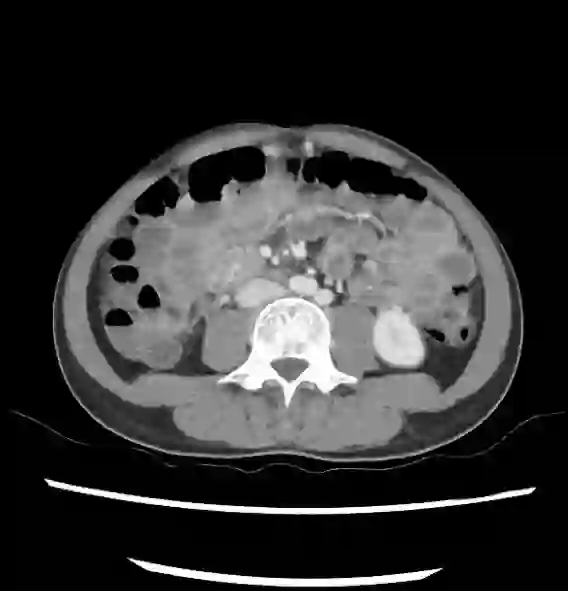

In this study, we aim to initiate the development of Radiology Foundation Model, termed as RadFM.We consider the construction of foundational models from the perspectives of data, model design, and evaluation thoroughly. Our contribution can be concluded as follows: (i), we construct a large-scale Medical Multi-modal Dataset, MedMD, consisting of 16M 2D and 3D medical scans. To the best of our knowledge, this is the first multi-modal dataset containing 3D medical scans. (ii), We propose an architecture that enables visually conditioned generative pre-training, allowing for the integration of text input interleaved with 2D or 3D medical scans to generate response for diverse radiologic tasks. The model was initially pre-trained on MedMD and subsequently domain-specific fine-tuned on RadMD, a radiologic cleaned version of MedMD, containing 3M radiologic visual-language pairs. (iii), we propose a new evaluation benchmark that comprises five tasks, aiming to comprehensively assess the capability of foundation models in handling practical clinical problems. Our experimental results confirm that RadFM significantly outperforms existing multi-modal foundation models. The codes, data, and model checkpoint will all be made publicly available to promote further research and development in the field.